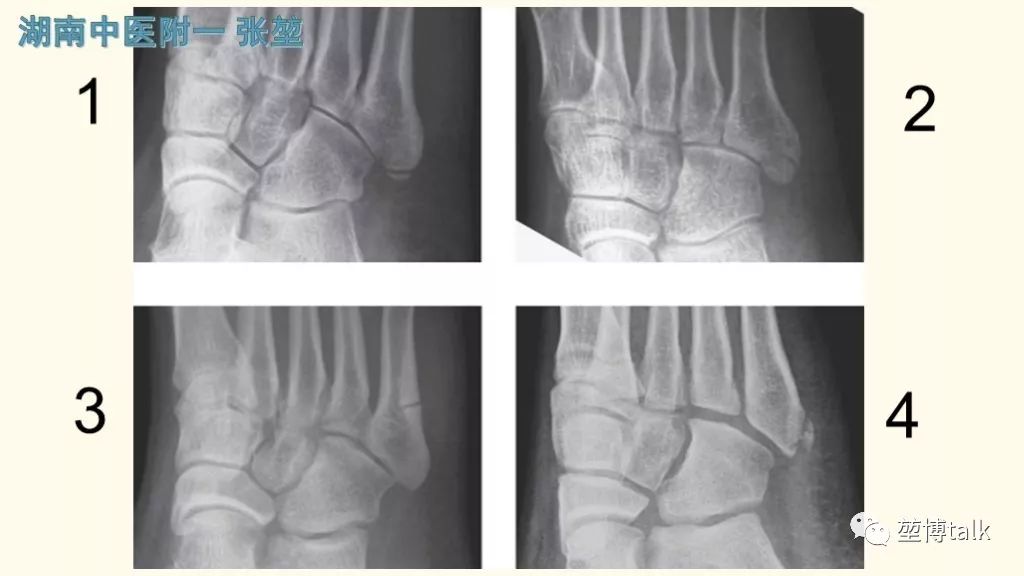

第五跖骨基底骨折